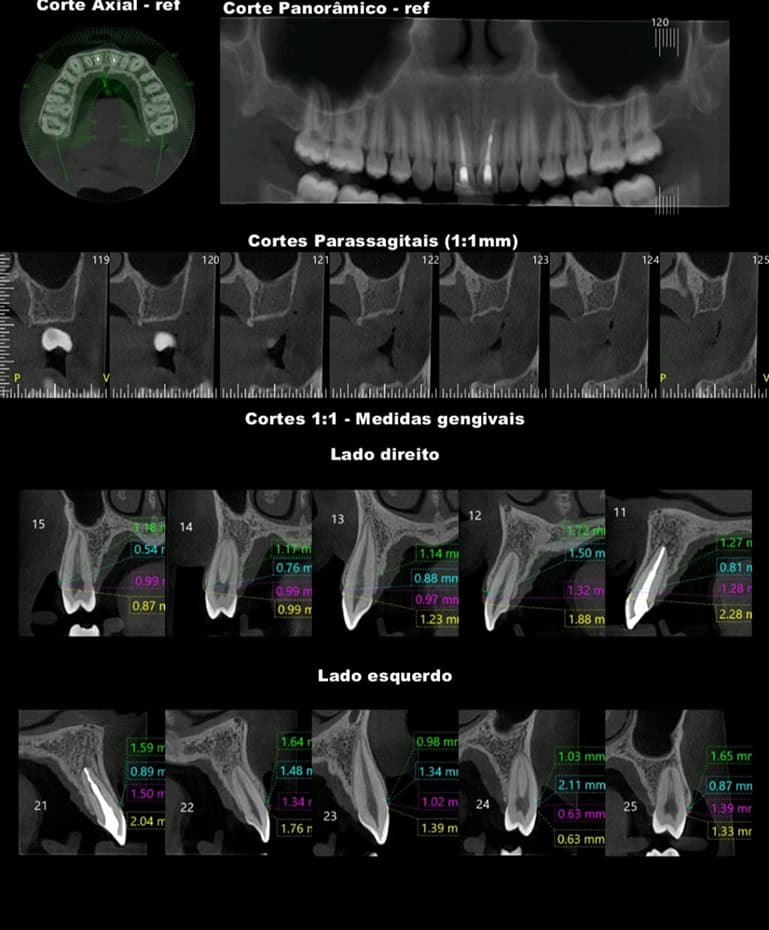

TOMOGRAFIA COMPUTADORIZADA DE ALTA RESOLUÇÃO por feixe Cone Bean - MORITA X800

• ATM´s

• MAXILA TOTAL

• MANDÍBULA TOTAL

• REGIÕES: Implantodontia, Periodontia, Cirurgia, Endodontia e Estomatologia